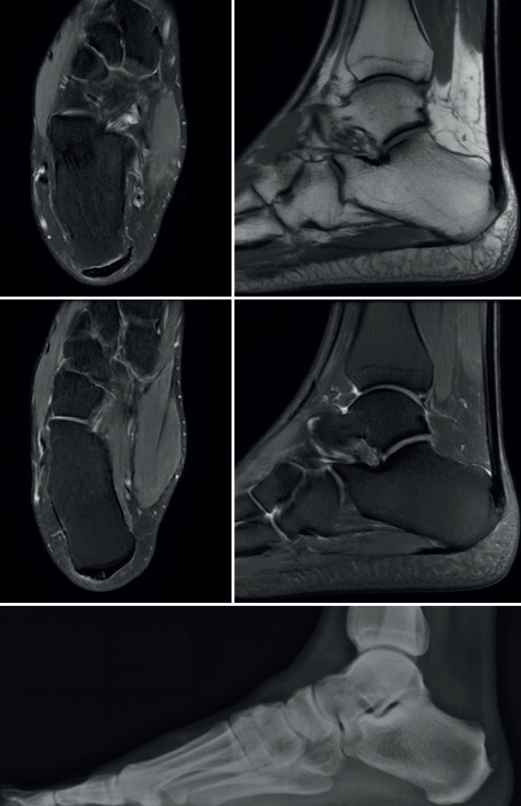

Durante el periodo comprendido entre marzo de 2015 y mayo de 2020, se incluyeron pacientes de ambos sexos, entre 18 y 60 años de edad, que tenían el diagnóstico de tendinopatía crónica de Aquiles y se les realizó una transferencia del tendón FLH. Todos los participantes tenían el diagnóstico por resonancia magnética o ultrasonidos y trataron los síntomas en el retropié (es decir, dolor, sensibilidad, hinchazón) de forma conservadora durante al menos 3 meses antes de la cirugía (Figura 1). El tratamiento consistió en el uso de antiinflamatorios no esteroideos (para pacientes sin contraindicaciones), calzado con talonera levantada y suave, hielo, ejercicios de estiramiento de la cadena posterior y fisioterapia(1,2).

Figura 1. Estudio radiológico que incluye resonancia magnética del tobillo y radiografía del pie del participante con tendinopatía insercional de Aquiles crónica.